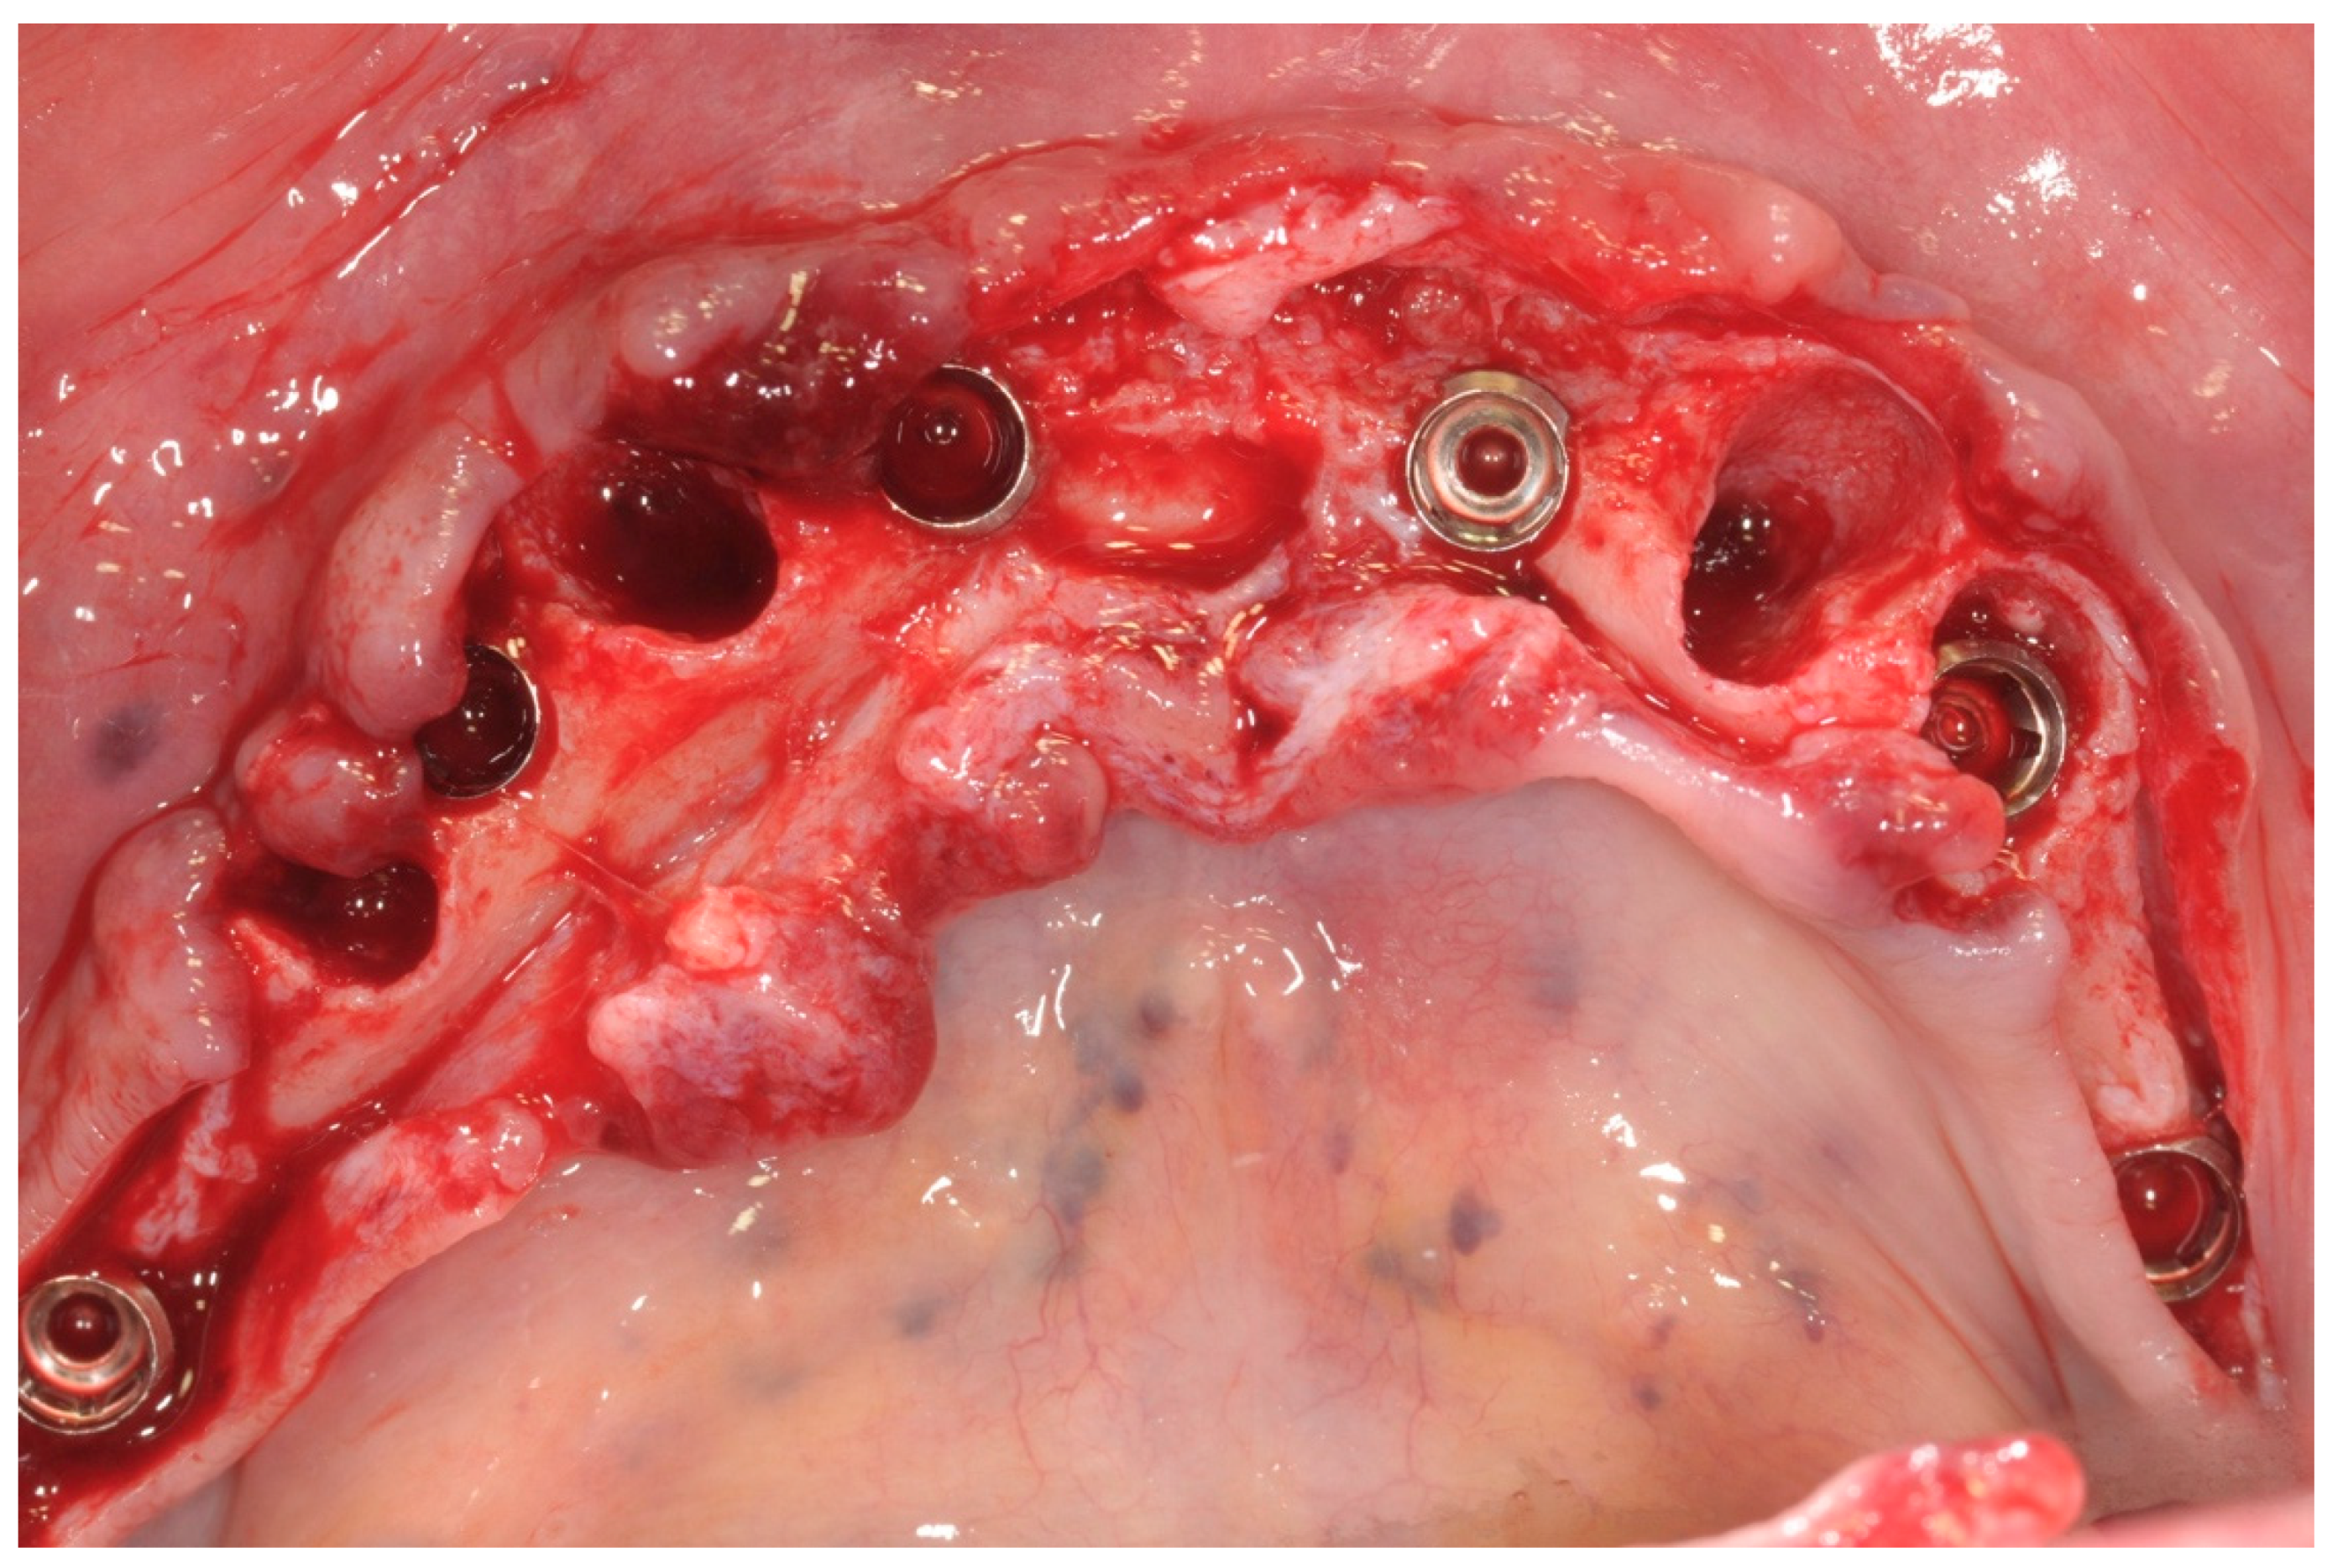

All patients were treated under local anesthesia, and patients received four, five, or six implants in the mandible according to the prosthetic treatment plan. In the case of tooth extraction sites, a periodontal probe was used to assess the integrity of the extraction socket’s bony walls and of the adjacent bone peaks to evaluate the feasibility of an immediate implant (Figure 2).

Figure 2. Operative site after tooth extractions.